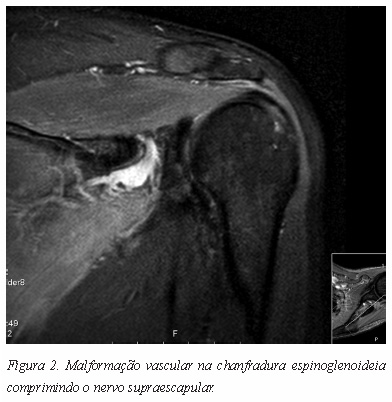

A compressão pode também acontecer na goteira supraescapular ou na chanfradura espinoglenoideia por um mecanismo direto, como seja a presença de um tumor dos tecidos moles, um tumor ósseo, uma malformação vascular, ou mesmo um quisto secundário a lesão capsular ou do labrum (Figuras 2 e 3).

Em doentes com uma estenose da goteira supraescapular ou da chanfradura espinoglenoideia por calcificação ou hipertrofia ligamentar existe uma maior predisposição para uma compressão do nervo a estes níveis.